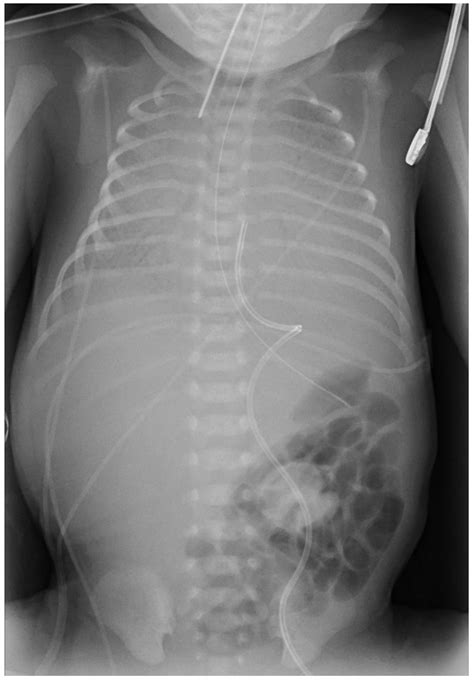

Once a Persistent Right Umbilical Vein is detected, the standard of care usually involves a multidisciplinary approach to ensure the pregnancy proceeds safely. This typically includes a fetal echocardiogram, which is a specialized ultrasound of the baby's heart, performed by a pediatric cardiologist or a perinatologist. The purpose of this scan is to look closely at the flow of blood and the structure of the heart chambers to ensure that the altered vascular path is not causing any undue stress.

Additionally, doctors may recommend a follow-up ultrasound in the third trimester to monitor the baby's growth and confirm that the amniotic fluid levels remain stable. In some instances, genetic counseling may be offered to discuss the findings, especially if other "soft markers" were noted on the anatomy scan. This process allows parents to make informed decisions and receive appropriate support throughout the remainder of the pregnancy.

For parents hearing the term Persistent Right Umbilical Vein, the most important takeaway is that the prognosis is highly favorable. The vast majority of infants born with this condition reach their full term and display no symptoms or health issues related to their fetal circulation. The liver functions normally, the heart develops correctly, and the child's development post-birth is typically no different from their peers.

The primary reason for the increased focus on this diagnosis is not the severity of the PRUV itself, but rather the necessity of confirming that it is truly isolated. By confirming the absence of other structural or genetic markers, doctors can provide parents with peace of mind. Most babies with an isolated PRUV require no special postnatal care, and they are usually discharged from the hospital just like any other healthy newborn.